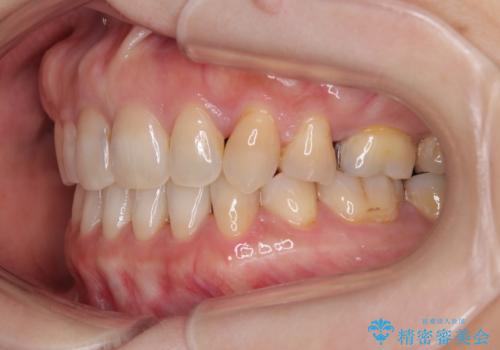

- 前歯のデコボコと口元の突出感を気にして来院された患者様です。

上下前歯がくちばしのように突出していたため、上下左右の第一小臼歯4本を抜歯し、ワイヤー装置にて矯正治療を行うこととしました。

上顎骨に対して下顎骨がやや前方位に位置しているため、歯肉退縮を回避するために下顎前歯をあまり内側に移動させることができない状況でしたが、十分に口元の突出感を改善することができました。